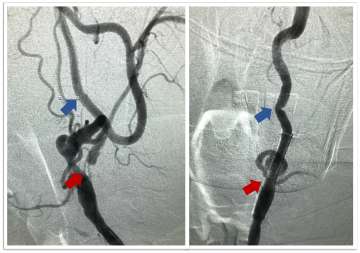

• Carotid Artery Stenting: This is a newer endovascular procedure performed from the inside of the blood vessels to open the stenosis. The surgeon uses small tubes and wires inserted into the wrist or groin arteries, navigated to the carotid artery in the neck. An umbrella is positioned above the narrowing to catch any debris and a stent is delivered to dilate the region of stenosis and hold the vessel open, improve flow and prevent future strokes (Figures 3 and 4).

Figure 3. Carotid Stenting – Pre-treatment (left) cerebral angiogram image demonstrating severe cervical internal carotid artery stenosis (red arrow) before treatment and the relatively normal artery downstream (blue arrow).